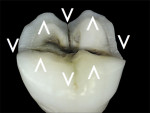

The clinical case involved a preparation of a vital tooth No. 26 with a substantially damaged occlusal surface from erosion (Figure 1 and Figure 2). The patient was a 27-year-old man, who frequently drank sparkling sweet drinks and had good oral hygiene. Demineralization of the enamel provided loss of hard tissues (index score = 3), and a conservative approach was taken.

The treatment goal was to obtain a complete, 2-mm-deep homothetic reduction of the occlusal surface. Each step involved a specific procedure that required the use of specific rotary instruments. Those steps included: creating guides grooves, performing the cusp reduction, and finishing the preparation.

The tip of the bur was positioned at the bottom of the mesial and distal marginal ridge. It was sweeped transversally, without adding to the depth of the groove. The sweeping motion was guided by the grooves. The morphology of the preparation, at this point, appeared as a combination of “V” shapes in the palatal-lingual and mesio-distal directions (Figure 9 and Figure 10). It formed a butt joint between the tooth and ceramic material (Figure 9 through Figure 11). Then a cylindrical-conical red diamond bur, with a total occlusal convergence of 7°, was used to polish the occlusal surface, particularly the rough edges and periphery.